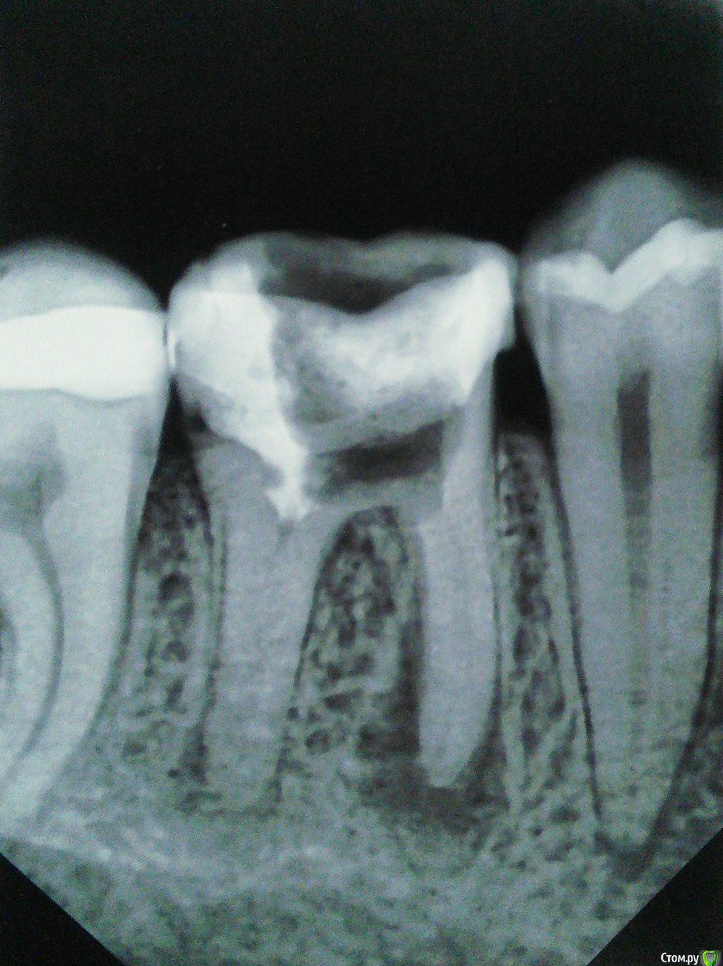

Bubnov Опубликовано 22 августа, 2017 Поделиться Опубликовано 22 августа, 2017 (изменено) Здравствуйте!В наличии:- Немного шатается 45-й зуб;- Припухла щека-челюсть, зуб почти всегда болит, десна воспалилась;- Заделанные резорцином (могу ошибаться) каналы зуба.Врач очистил зуб от пломбы и уперся в эти корни, которые, как он сказал - "прочистить и добраться до воспаления невозможно". Подскажите, возможно ли такое вылечить? Изменено 22 августа, 2017 пользователем Bubnov Ссылка на комментарий

St. Опубликовано 22 августа, 2017 Поделиться Опубликовано 22 августа, 2017 (изменено) Да, скорее всего резорцин. Гипотетически воспаление на корнях возможно лечить, но учитывая сколько от зуба осталось своих тканей, я за удаление. Зуб по номеру 46 Изменено 22 августа, 2017 пользователем St. 2 Ссылка на комментарий

Бендер Опубликовано 22 августа, 2017 Поделиться Опубликовано 22 августа, 2017 Прогноз даже при идеальном лечении каналов не самый радужный Ссылка на комментарий

Bubnov Опубликовано 23 августа, 2017 Автор Поделиться Опубликовано 23 августа, 2017 Печально. Думал хоть коронку или штифт какой вставить. Посмотрите еще, пожалуйста, на зуб что левее сабжа. Он так же болен? Ссылка на комментарий